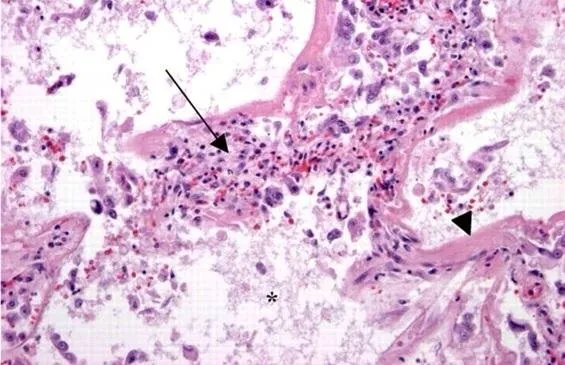

Profilaktyka HIV, na zdjęciu widać mikroglej po kontakcie z wirusem HIV. Obraz wskazuje na encefalopatię powodowaną przez HIV.

Profilaktyka HIV

Polska jest bardzo specyficznym krajem, co podkreślane jest na każdym kroku poprzez kolejne nielogiczne decyzje polityczne. W tym rozgardiaszu cierpi edukacja jak i postawy moralne mieszkańców kraju. Egzemplifikacją są dane świadczące o tym, że Polska to kraj o najniższej wśród krajów europejskich świadomości na temat zakażeń jak i profilaktyki HIV. Dodatkowo 50-70% osób seropozytywnych nie